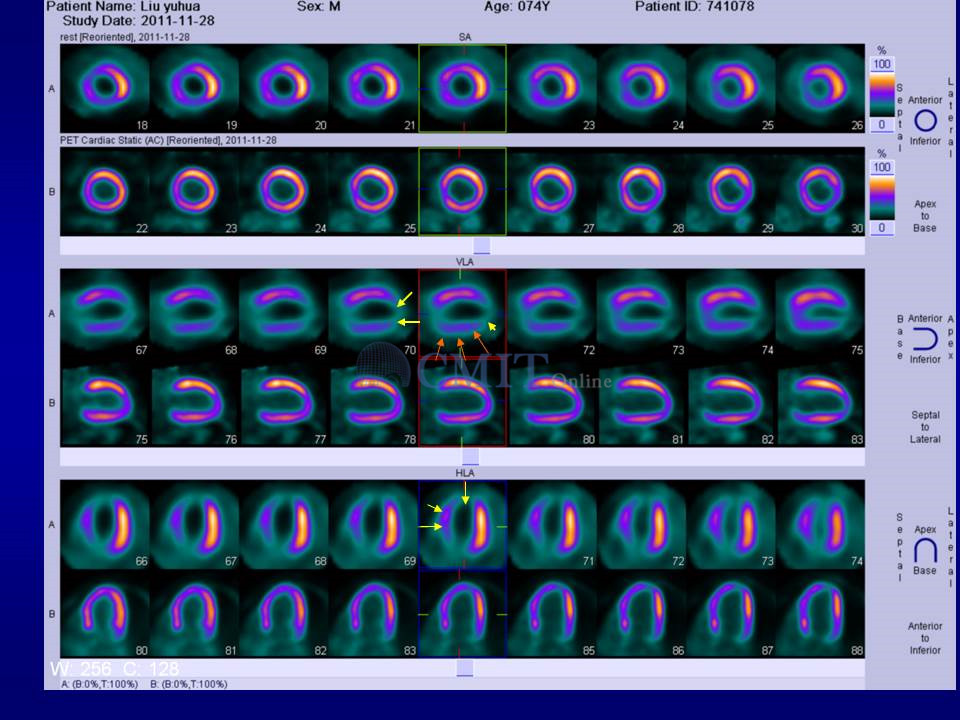

心肌梗死后完全闭塞病变,需要开通闭塞血管吗?——核素心肌显像用于评价存活心肌

首都医科大学附属北京安贞医院

张晓丽